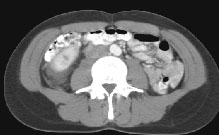

Fig.1 Fig.2 Fig.3

HELICAL CT FINDINGS: The CT was performed on AIC’s multi-slice helical CT (MSCT) scanner. Images with 5 mm collimation were obtained before, immediately following and 5-10 minutes after power injection of IV contrast. The region of the appendix was unremarkable. However, the right kidney and perinephric region were abnormal. Fig. 1 and Fig. 2 illustrate patchy and wedge-shaped low attenuation areas in the right kidney, and Fig. 3 shows stranding/infiltration of perinephric fat around the lower pole consistent with inflammatory changes (arrows).

DIAGNOSIS: The CT images are most compatible with acute pyelonephritis (APN) even without any laboratory results. Shortly after, results of blood work and urinalysis revealed leukocytosis and pyuria substantiating the CT diagnosis.